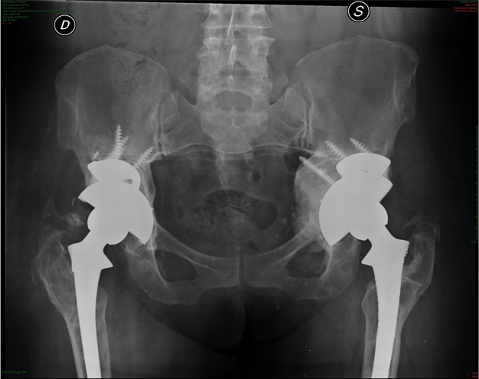

L’intervento di revisione della protesi di anca consiste nella rimozione (espianto) della vecchia protesi deteriorata e/o malfunzionante e la sua sostituzione con un nuovo impianto.

La rimozione e sostituzione della protesi si rende necessaria a causa del suo allentamento che può derivare sostanzialmente o da un problema settico (legato ad una infezione), oppure da un problema meccanico cosiddetto asettico (usura delle componenti protesiche), condizioni entrambe che possono richiedere un intervento di revisione a distanza di poche settimane o pochi mesi dal primo intervento (a breve termine). Le ragioni delle revisioni a distanza di anni dal primo intervento (a lungo termine) hanno invece a che fare con un deterioramento dell'impianto protesico.

- mobilizzazione asettica delle componenti protesiche: la liberazione di detriti all'interfaccia articolare (soprattutto particelle di polietilene) può indurre una reazione irritativa nell'osso circostante (osteolisi peri-protesica) culminante nel riassorbimento e quindi nello scollamento delle componenti acetabolare e femorale, che dovrebbero essere integrate. Mentre l’irritazione dell’osso è sostanzialmente asintomatica, la mobilizzazione è dolorosa e ricorda al paziente il dolore artrosico precedente la protesizzazione;

Le protesi destinate alla revisione sono, di solito, leggermente diverse da quelle usate nei primi interventi, Infatti, Gli Impianti da revisione sono realizzati in modo da offrire una elevata stabilità’ meccanica primaria ed una alta capacità osteoinduttiva, ovvero la capacità di integrazione e ricrescita ossea. Spesso si rendono necessari trapianti ossei per gestire i casi in cui si verifichi la mancanza di osso del paziente.